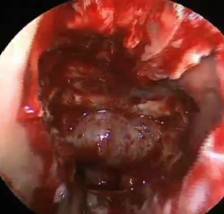

根据内镜和放射学检查结果,内镜手术可以从一侧鼻腔进行,也可以从两侧鼻腔进行。经鼻腔内镜手术利用鼻腔的天然间隙作为手术通道,直接达到蝶窦前壁,开放蝶窦,暴露鞍底后在内镜明视下,用吸引器、剥离子等沿着垂体窝底壁清除肿瘤。内镜手术大大缩短手术时间,并减少了对正常组织的损伤。

内镜手术照明好,能放大,视野清楚,能更准确地辨别肿瘤组织及邻近的重要结构。内镜手术中可应用不同角度的内窥镜,对蝶窦和蝶鞍结构做全景观察,可不同角度辨别颈动脉管、视神经管及骨壁生理性缺损等重要结构的变化。垂体手术肿瘤残留最常发生在鞍膈和海绵窦之间的角落,而这个区域在显微镜下通常看不见,而内镜能进入鞍内观察是否有肿瘤组织的残存,在直视下去除常规显微镜手术无法看见的肿瘤。内镜手术增加了手术的准确性和安全性,减少了术中危险和术后并发症,而同时能最大限度保留正常的垂体组织。